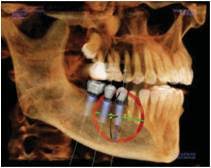

Dental cone beam computed tomography (CT) is a special type of x-ray machine used in situations where regular dental or facial x-rays are not sufficient. It is not used routinely because the radiation exposure from this scanner is significantly more than regular dental x-rays. See the Safety page for more information about x-rays. This type of CT scanner uses a special type of technology to generate three dimensional (3-D) images of dental structures, soft tissues, nerve paths and bone in the craniofacial region in a single scan. Images obtained with cone beam CT allow for more precise treatment planning.

Cone beam CT provides detailed images of the bone and is performed to evaluate diseases of the jaw, dentition, bony structures of the face, nasal cavity and sinuses. It does not provide the full diagnostic information available with conventional CT, particularly in evaluation of soft tissue structures such as muscles, lymph nodes, glands and nerves. However, cone beam CT has the advantage of lower radiation exposure compared to conventional CT.

- accurate placement of dental implants.

- Cone beam CT scans provide more information that conventional dental x-ray, allowing for more precise treatment planning.